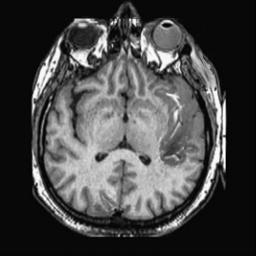

To demonstrate the effectiveness and efficiency of the proposed image fusion method , we conduct a set of comparative experiments on three image datasets. The first is composed by 8 pairs of multi-modal medical images and the second one contains 15 pairs of multi-focus gray or color natural images. These two datasets are often used in many related papers and some examples are shown in Figure 3(a) and Figure 3(b). The third one is a new multi-focus cervical cell image dataset collected by ourselves, which consists of 15 groups of color images and each group contains a series of multi-focus cervix cell images with size of or , etc. Some source examples are shown in Figure 3(c). Our source code implemented in C++ along with the new multi-focus cervical cell image dataset is available online.

We first evaluate the performance of the proposed method under varying total number of octaves and number of layers sampled per octave. The fused images of a pair of multi-modal medical images with different and are shown in Figure 4. In this example, on the one hand, when only 1 or 2 octaves are involved in constructing the DoG pyramid, the fused images fail to keep the integrity information of large size objects (e.g. eyeballs), while by increasing the value of , the integrity information of eyeballs is preserved. On the other hand, although not as significant as the increase of octave numbers , the fused image can contain more details by the increase of layer numbers . The corresponding objective quality metrics are shown in Figure 5. As shown in Figure 5(a), most of the metric values are improved as the number of octaves increases with the fixed layer numbers 3 in the global tendency and each of them tends to be stable when the number of octaves is 5. To get a relatively good quality from Figure 5(b), we can notice that some of the metric values can get a good performance when the number of layers is 3, such as the MI, SSIM, QI and VIF, though there are only a little change of all the metric values by increasing the number of layers with the fixed octave numbers 5. Because it will result in more computation burden with the increase of the value and , and for different kinds of source images, there are different performance with the diverse parameter settings. To get a trade-off between them in our experiments, we set for the multi-modal dataset, for the natural datasets and for the multi-focus cell dataset, respectively.

Figure 6 shows the fused images obtained by different methods with the multi-modal source images shown in Figure 3(a). As shown in these figures, the proposed method can produce images which preserve the complementary information of different source images well. Moreover, due to the scale-invariant structure saliency selection, our method can keep the integrity information of large size objects and the visual details simultaneously. Although the fused image generated by other methods can also capture the details to some extent, all of them fail to keep the integrity information of large size objects such as the eyeballs. Furthermore, from Figure 6(k)-6(t), the DTCWT, GFF, IM and NSCT methods may decrease the brightness and contrast while the proposed method can preserve these features and details without producing visible artifacts and brightness distortions.